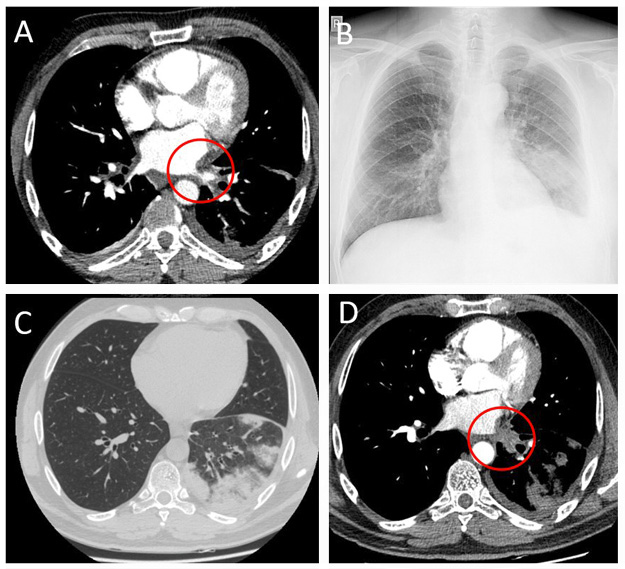

On admission a chest X-ray showed subtle patchy consolidations in the left lower lobe of the lung (Fi­gure 1B). A chest CT scan showed patchy consolidations, areas of atelectasis of the left lower lobe parenchyma (Figure 1C), and the absence of communication between the left lower pulmonary vein and the left atrium (Figure 1D). A quantitative ventilation/perfusion scan (99mTc-MAA 98MBq) revealed that the left lung was receiving only 15% of the overall lung perfusion with no perfusion to the left lower lobe (Figure 2). Bronchoscopy found striking hyperemia and brisk bleeding to touch of the mid and distal left lower lobe bronchus. Based on instrumental and clinical findings, it was decided to perform balloon angioplasty with further stent implantation. However, the procedure was unsuccessful, due to an invisible lumen or dimple, that can be probed in the vein.

Figure 2. Quantitative ventilation/perfusion scan

A radiological examination may show only some non-specific abnormalities such as pulmonary infiltrates or pleural effusion, therefore specific visualization of the pulmonary vein is always necessary to confirm the diagnosis [1, 2]. A V/Q scan could be an important tool to assess the severity of stenosis [8]. In analyzed cases, diagnosis of PVS or PVO was usually confirmed by imaging techniques. In eight out of 11 cases, as well as in ours, a total PVO was confirmed. Total PV thrombosis was found in one case, and in two cases, severe PVS. However, a V/Q scan showing a significant reduction of lung perfusion was performed only in two previous cases.